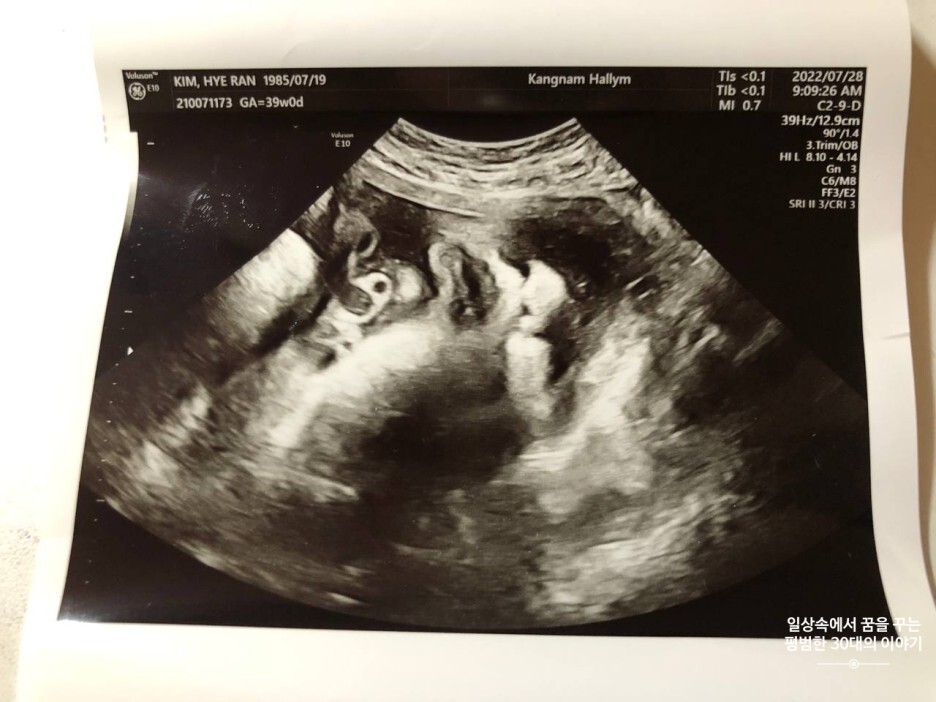

7월 28일 목요일(39주 차 0일)

BPD(Biparietal Diameter, 위에서 볼 때 태아 머리 단면의 가장 긴 길이): 9.57cm

HC(Head Circumference, 태아 머리둘레): 34.17cm

AC(Abdominal Circumference, 배 둘레): 36.58cm

EDD(Expected Date of Delivery, 출산 예정일): 2022년 8월 4일

FL(Femur Length, 허벅지뼈 길이): 7.21cm

GA(Gestational Age, 임신 주차): 39주 차 0일

EFW(Estimated Fatal Weight, 태아 예상 체중)=EBW(Estimated Body Weight): 3850g

FHR(Fetal Heart Rate, 심장박동 수): 135bpm

CL(Cervical Length, 자궁경부 길이): 정상

AF(Amniotic Fluid, 양수): 정상